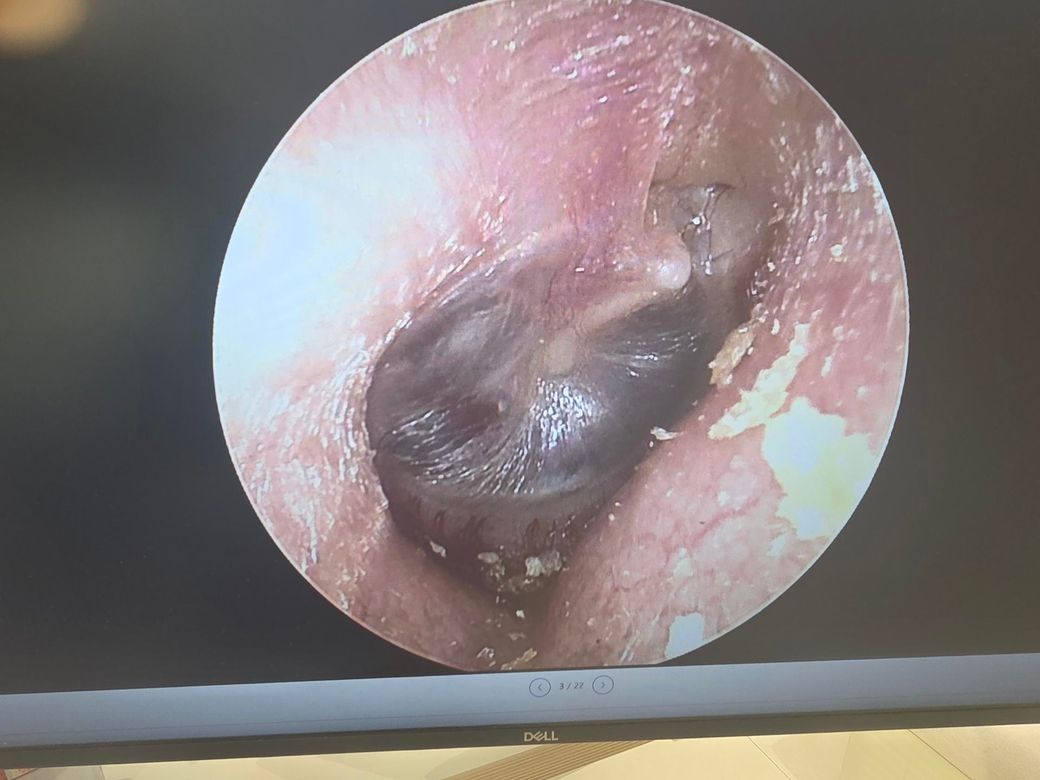

양측 고막 사진입니다. 병원마다 하는 얘기가 다릅니다. 이관은 개방이니까 플러그 넣어야한다 폐쇠니까 풍선확장술 해야한다 나뉘고요. 고막은 retraction 이랑 Adhesion 이 있다고 어느 병원에선 환기관 넣아야한다 어느병원에선 물이 차있는게 아니라서 안넣어도 된다 라고 합니다

어떤 소견이 맞고 어떤 치료방법이 맞을지 궁금하네요 그리고 현재 고막 상태는 어떤가요? 발사바 했을때 사진도 같이 첨부합니다

• 제시하신 고막 사진은 전반적으로 심한 함몰(retraction)과 일부 부위의 유착(adhesion)이 의심되는 소견입니다. 특히 고막이 중이 쪽으로 깊게 당겨져 있고, 광택이 줄어들며 특정 부위가 고정된 형태로 보입니다. 이는 단순한 일시적 음압 상태를 넘어서, 만성적인 이관 기능 이상에 의해 구조 변화가 진행된 단계로 해석하는 것이 타당합니다.

병태생리를 기준으로 정리하면, 이관 기능이 저하되면 중이 내 음압이 지속되면서 고막이 안쪽으로 빨려 들어가고, 이 상태가 지속되면 고막이 중이 구조물과 붙는 유착이 발생합니다. 이 단계에서는 단순한 이관 개방/폐쇄 개념만으로 설명이 어려워지고, “기능 이상 + 구조 변화”가 동시에 존재하는 상태로 보는 것이 맞습니다.